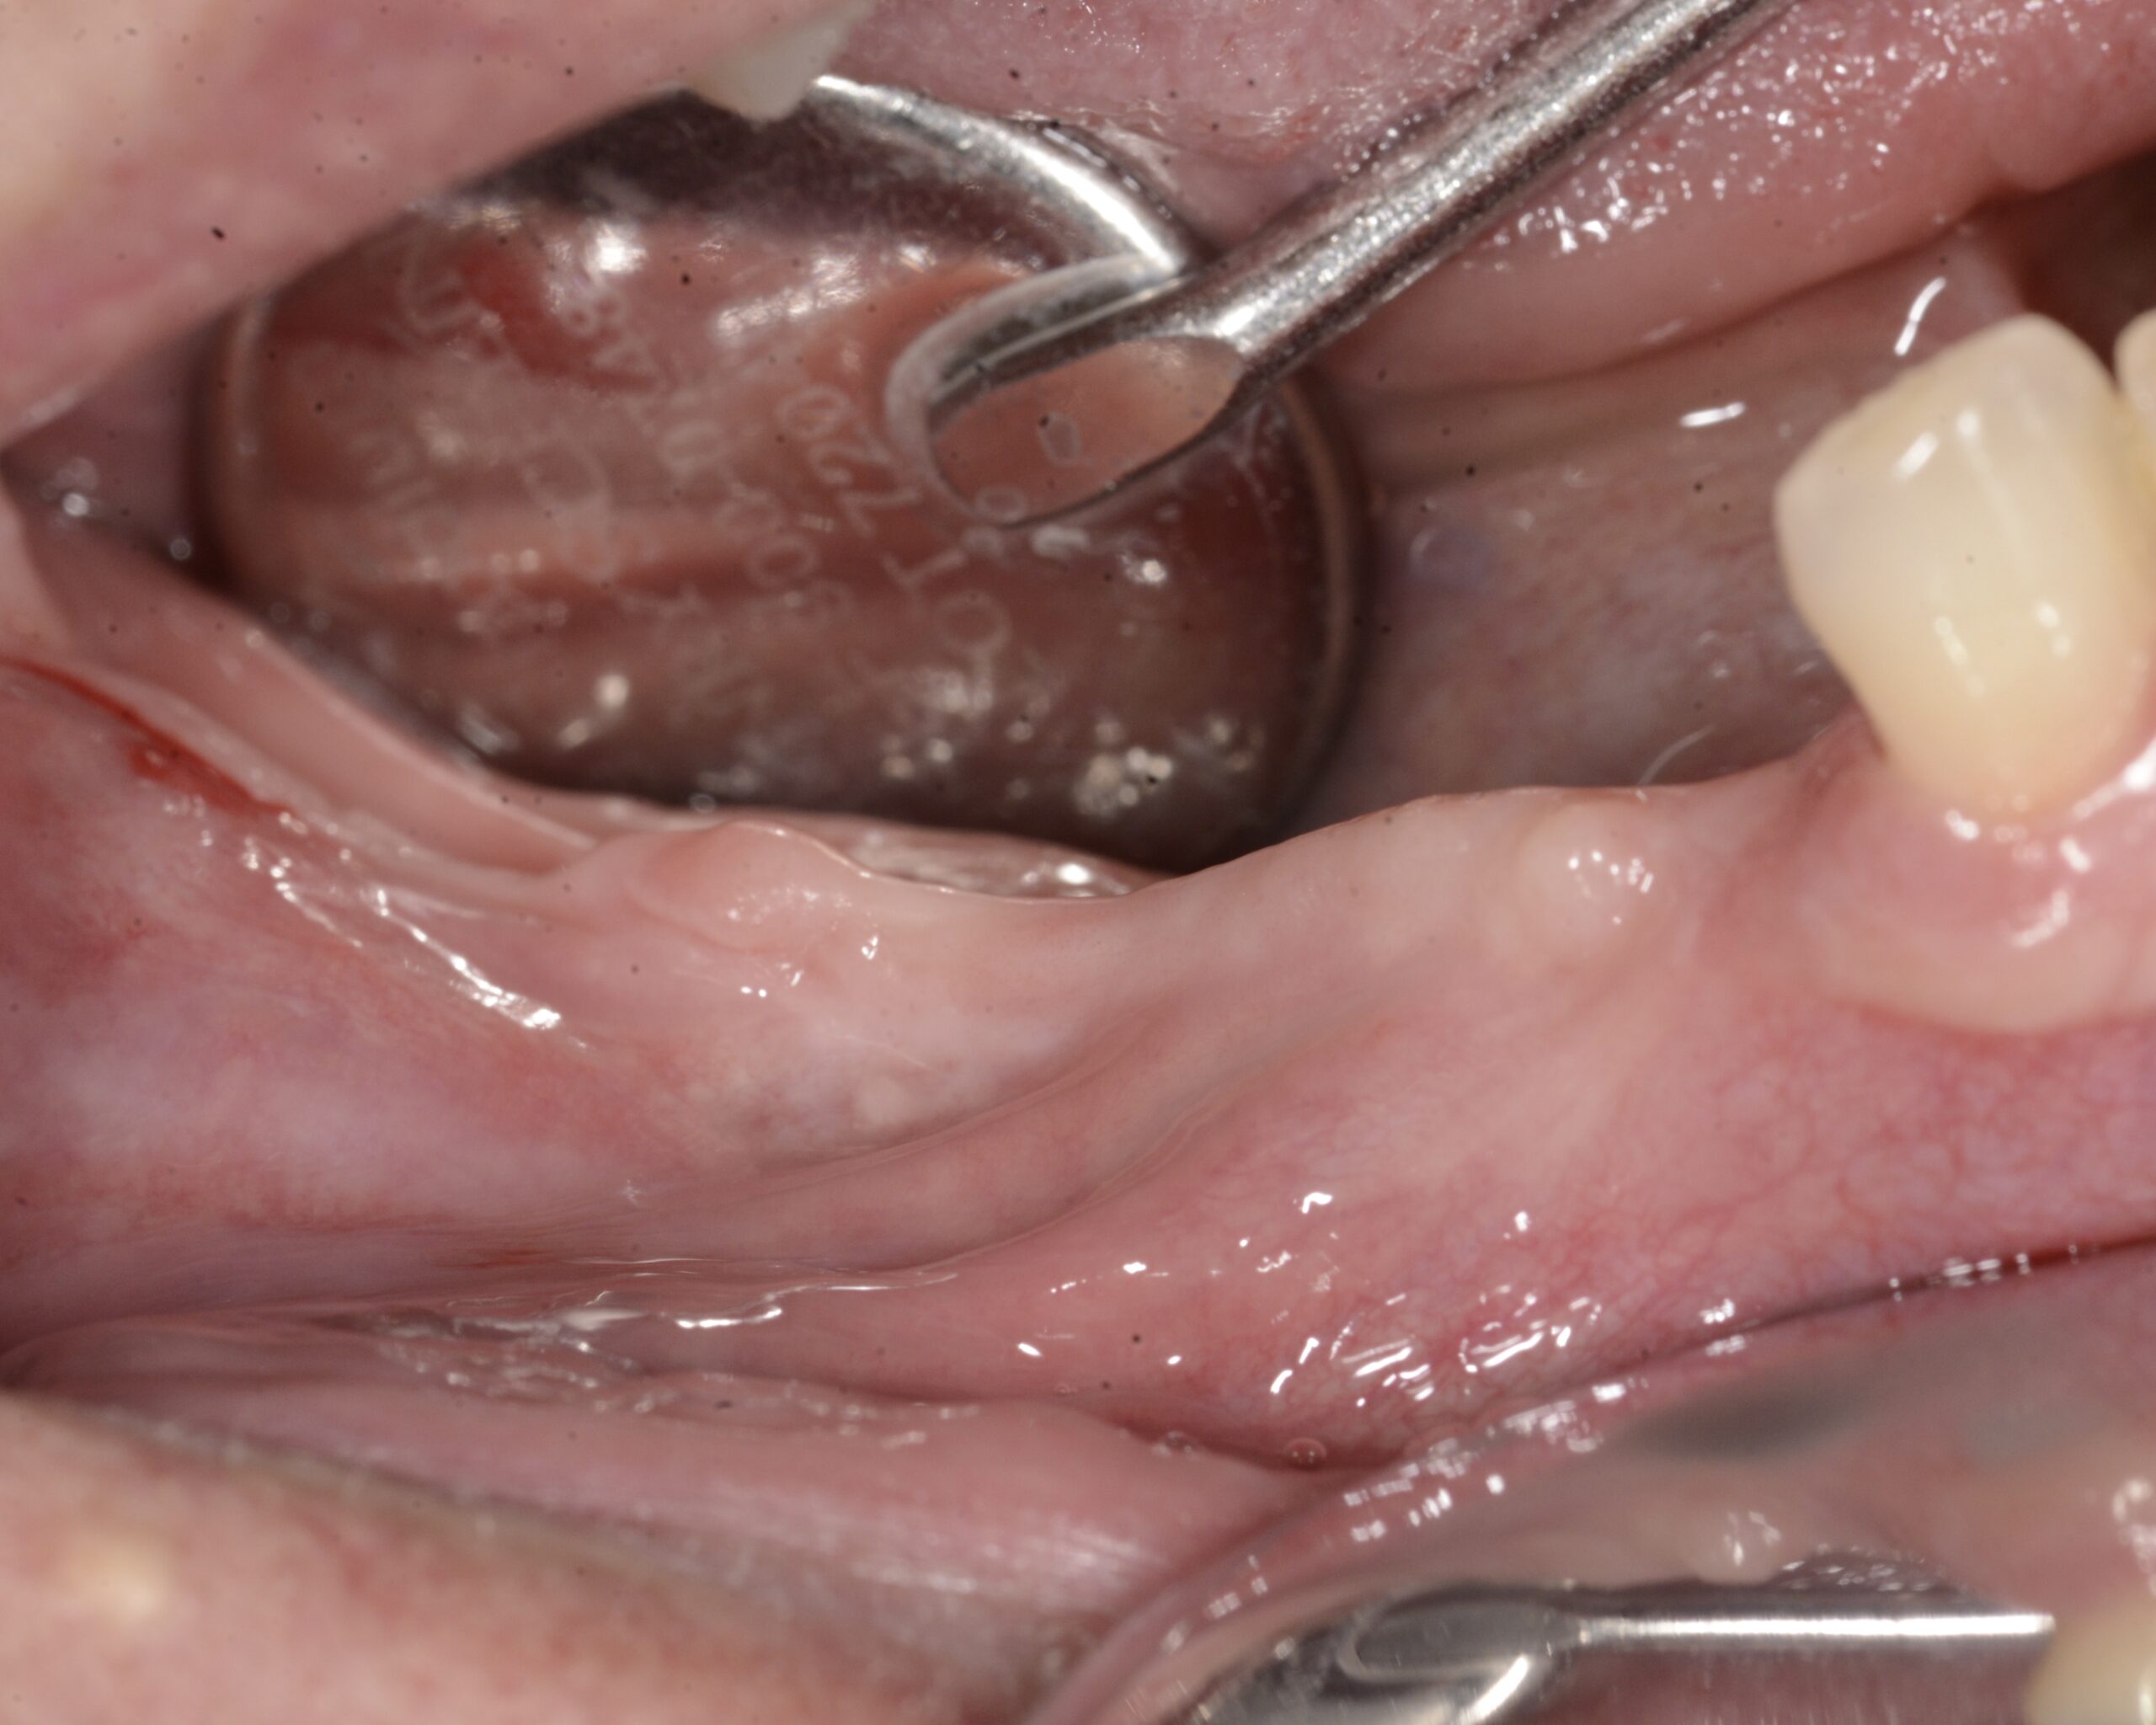

L’intervento inizia con un’incisione crestale sulla sella edentula, proseguita in direzione mesiale intrasulculare all’elemento 4.3 e completata con un’incisione di rilascio mesiale in modo da permettere la chiara visualizzazione del sito. Si esegue la scheletrizzazione del corpo mandibolare andando a identificare e proteggere il nervo mentoniero, che alla sua fuoriuscita dal foro omonimo presenta aspetto bifido (Figura 4). Viene infine eseguito il rilascio dei lembi mediante incisioni periostali affinché questi possano essere successivamente riposizionati e suturati passivamente.